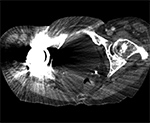

Streak and Shadow Artifact. (A) Axial CT image of the lumbar spine demonstrates extensive high attenuation linear streak and splay artifact secondary to posterior spinal fusion hardware.  (B) Axial CT image of the left hip demonstrates linear low attention shadow artifact propagating along the axis of greatest metal cross-section, which obscures the femoral neck.